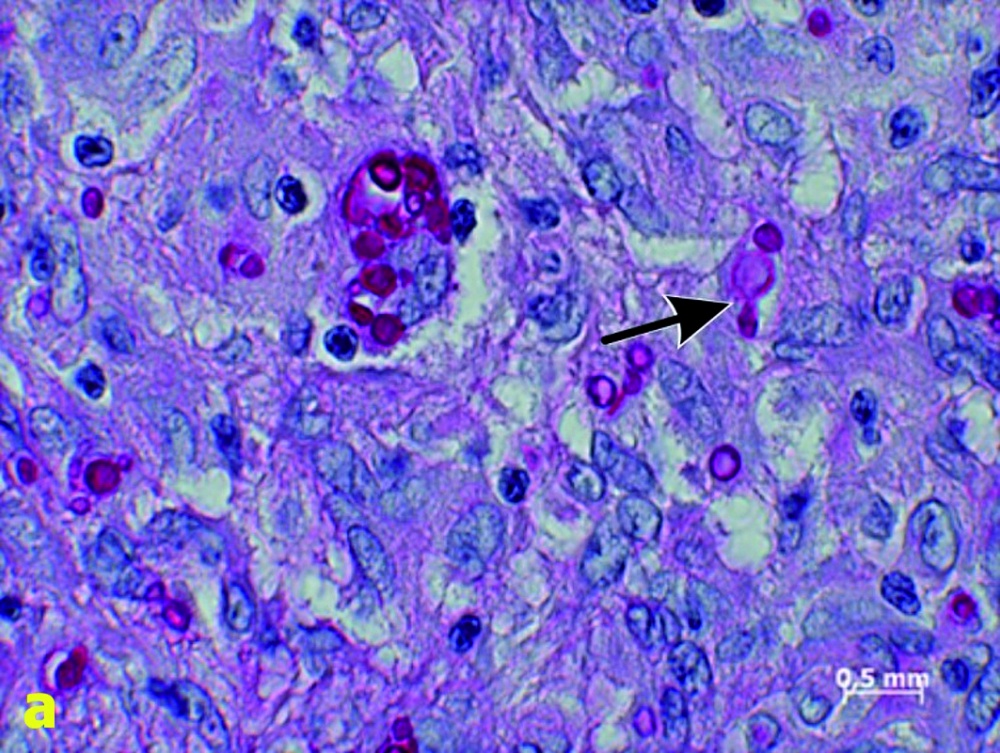

Hierzu wurden insgesamt siebzehn formalinfixierte paraffinierte Gewebeproben histologisch umfassend charakterisiert. Zu den histologischen Diagnosen gehörten die Chromoblastomykose (n = 3), die Coccidioidomykose (n = 2), die Histoplasmose (n = 3), die Histoplasmose oder Kryptokokkose bei histologisch schwieriger Diskriminierbarkeit (n = 1), die Mukormykose (n = 2), das Myzetom (n = 3) und die Rhinosporidiose (n = 2) (Abbildung 1).

(Bildquellen: Bildausschnitte aus [18])